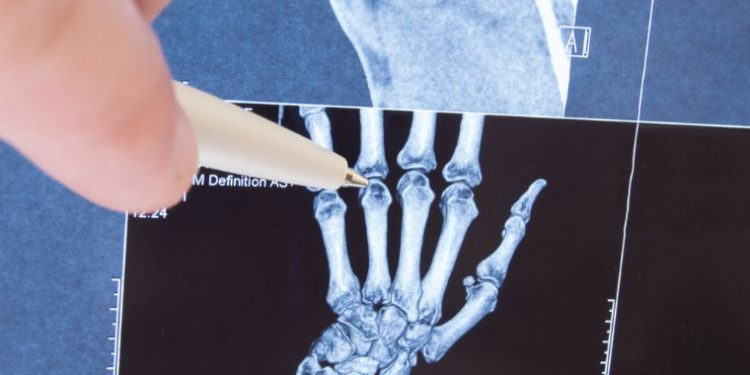

A doctor can diagnose this disease by asking questions and doing a physical exam. A blood test, X-rays and bone scan can help rule out other conditions.